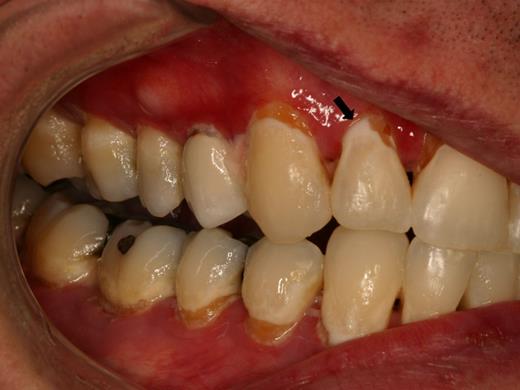

Patients with salivary gland cGVHD are at risk for developing secondary infectious complications because of diminished anticariogenic and antifungal activities. In addition to the effects on teeth (Figure 7), patients are at significant risk for recurrent oral candidiasis, especially if there is ongoing topical corticosteroid therapy for management of mucosal cGVHD, which suppresses mucosal immunity (see “Infections”; Figure 8).

Rampant cervical dental caries affecting all of the teeth in a patient with cGVHD of the salivary glands. Demineralization changes (arrow) appear chalky white.

Patients with salivary gland cGVHD are at risk for developing secondary infectious complications because of diminished anticariogenic and antifungal activities. The development of accelerated and often rampant dental caries is a largely under-recognized complication of oral cGVHD that can develop rapidly, leading to extensive dental treatment, extraction of teeth, and significant social and economic costs.65-67 Before the development of frank carious lesions, the teeth may demonstrate demineralization changes along the cervical margins, characterized by a white and chalky appearance (Figure 7). Dental caries tend to develop at the cervical margins and interproximal surfaces where dental plaque accumulates because of lack of salivary flow. Exacerbating this problem is that patients with oral mucosal cGVHD may neglect oral hygiene because of discomfort associated with tooth brushing, compounding the effects of salivary gland changes. In addition to the effects on teeth, patients with salivary gland cGVHD are at significant risk for recurrent oral candidiasis, especially if there is ongoing topical corticosteroid therapy.

Prevention of dental caries is a critical component of salivary gland cGVHD management, and we initiate these measures in all patients with clinically significant disease (Table 4). Patients should be continuously reminded of the importance of maintaining a noncariogenic diet and good oral hygiene. In patients with severe salivary gland hypofunction, even when tooth brushing after eating is not feasible, patients should be instructed to rinse their mouths well with water. Prescription 1.1% sodium fluoride gel should be applied to the teeth nightly, either using a toothbrush to “paint on” to the teeth, or via custom-fitting trays that can be fabricated by the patient's dentist.68,69 In addition to topical fluoride, emerging evidence supports the use of a calcium/phosphate-based remineralizing agent (eg, GC MI Paste Plus, GC America), which can be applied just before topical fluoride.70,71 Dentists can place fluoride varnish twice annually during recall visits for further protection. Bitewing radiographs should be obtained on an annual basis to screen for interproximal decay (Figure 15), and areas of decay should be treated promptly and definitively (ie, the full extent of caries must be removed as risk for recurrent decay is high).